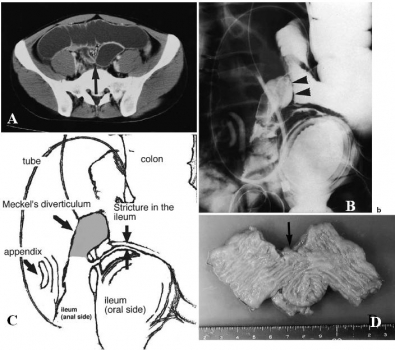

Hình 14: Tắc ruột non do xoắn túi thừa Meckel ở bệnh nhân nam 30 tuổi. A, x quang bụng nằm ngửa, B chụp bụng đứng. Một bóng khí hình oval chứa nhiều nốt vôi dạng viền bên trong ở ¼ bụng dưới phải (mũi tên). Sau phẫu thuật là túi thừa Meckel bị xoắn (Angela D. Levy, Christine M. Hobbs (2004). Meckel Diverticulum: Radiologic Features with Pathologic Correlation. RadioGraphics 24:578)

Hình 15: Tắc ruột do lồng ở bệnh nhân nữ 41 tuổi bị nhồi máu và hoại tử túi thừa Meckel. A, các quai ruột non trên đoạn tắc giãn lớn. B, đoạn hồi tràng bị lồng, đoạn ruột non thành dày phù nề (đầu mũi tên). Điểm giữa đoạn lồng có mỡ giảm đậm độ (mũi tên). Sau phẫu thuật : nhồi máu và hoại tử túi thừa Meckel là nguyên nhân gây lồng hồi – hồi tràng. (Angela D. Levy, Christine M. Hobbs (2004). Meckel Diverticulum: Radiologic Features with Pathologic Correlation. RadioGraphics; 24:578)

Khi túi thừa Meckel có dải xơ nối với rốn hoặc nối với mạc treo, hoặc đầu tận cùng túi thừa Meckel dính với mạc treo thì sẽ trở thành cái bẫy cho các quai ruột non chui vào gây tắc ruột.

Hình 16: Tắc ruột do dải xơ của túi thừa Meckel ở bệnh nhân nam 17 tuổi. Hình ảnh phẫu thuật cho thấy dải xơ nối túi thừa Meckel và mạc treo, bên trong chứa mạch máu nuôi túi thừa.(Aziz Sumer et al (2010). Small Bowel Obstruction due to Mesodiverticular Band of Meckel’s Diverticulum: A Case Report. Hindawi Publishing Corporation Case Reports in Medicine. Article ID 901456; p2)

Hình 17: Hoại tử hồi tràng do chui vào thòng lòng được tạo bởi đầu tận cùng túi thừa Meckel dính với măt lưng mạc treo ở bệnh nhân nam 32 tuổi. A, CT quai ruột non dãn lớn, đoạn hồi – manh tràng xẹp nên nghi ngờ tắc ở hồi tràng. B, phẫu thuật: túi thừa Meckel và đoạn hồi tràng bị hoại tử. (Oguzhan KARATEPE. Cem DURAL et al (2008). Rare Complication of Meckel’s Diverticulum: Loop Formation of Diverticulum. Turk J Med Sci; 38 (1): 92.)

Hình 17C: Hình vẽ mô tả quai ruột non chui vào thòng lòng của túi thừa Meckel dính đầu tận cùng với mạc treo.

Tắc ruột do túi thừa Meckel dính vào thành bụng sau rất hiếm gặp và đã được ghi nhận.

Hình 18: A, CT các quai ruội non dãn, hồi tràng dính vào thành bụng sau (mũi tên). B, x quang thấy ổ đọng thuốc tròn khoảng 5 cm (đầu mũi tên). C, Hình mô tả vị trí túi thừa Meckel. D, đại thể: túi thừa Meckel, cổ túi thừa dính vào thành bụng sau (mũi tên), không phát hiện viêm hay loét. (C. Yamamoto et al (2003).: Meckel’s diverticulum adherent to abdominal wall. Journal of Gastroenterolory ; 38:195)